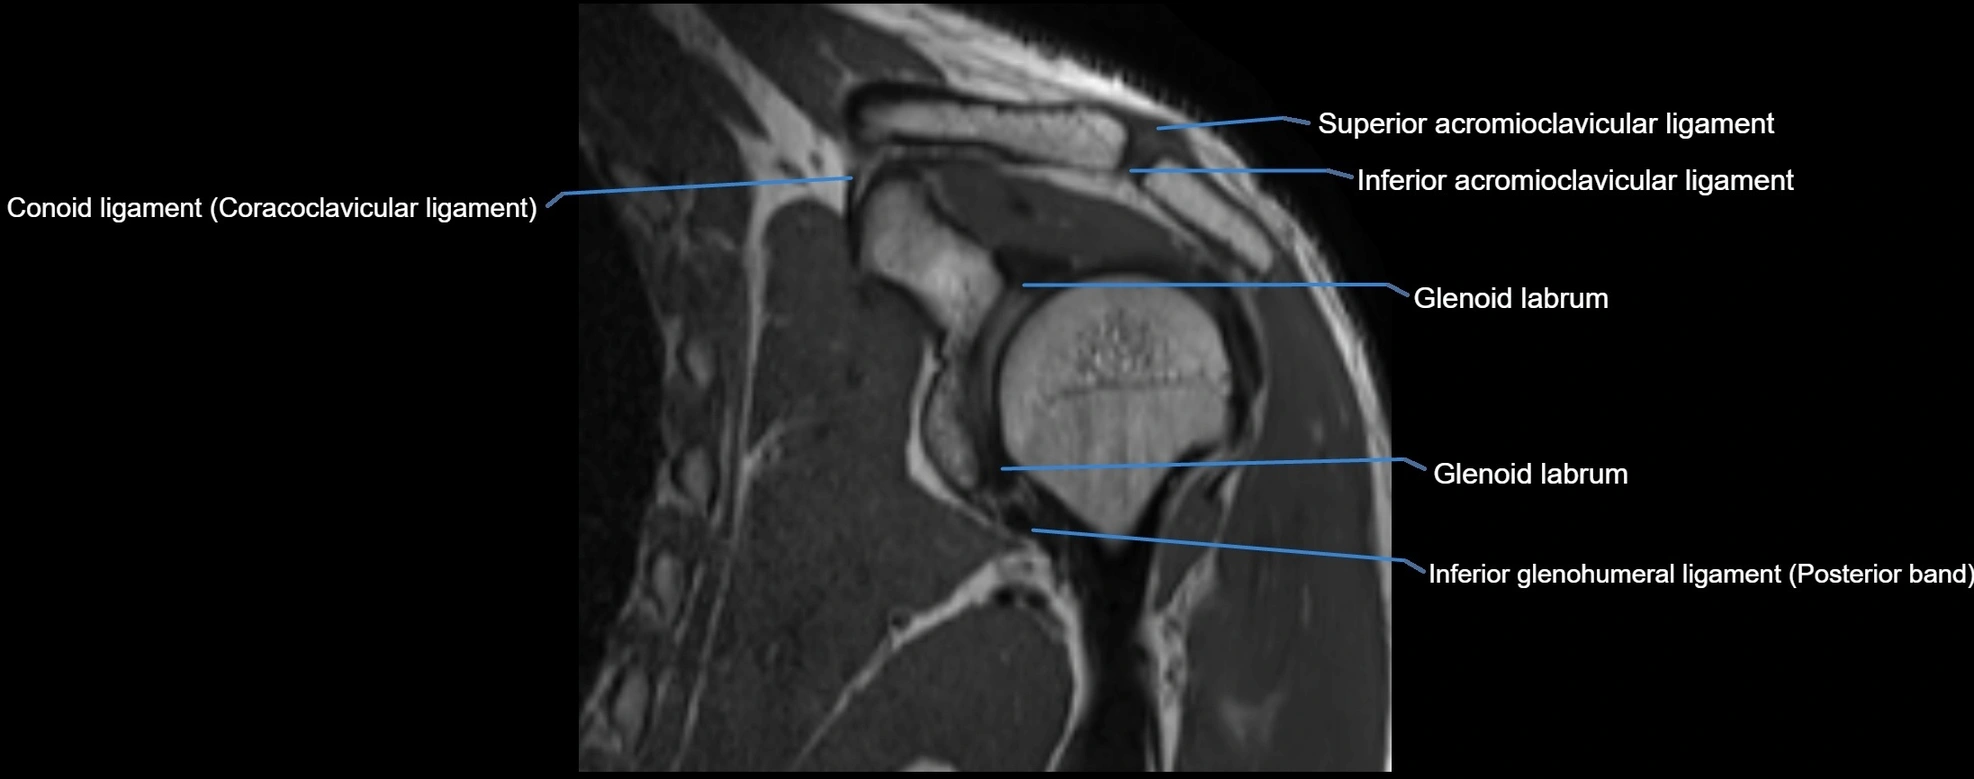

MRI images

image